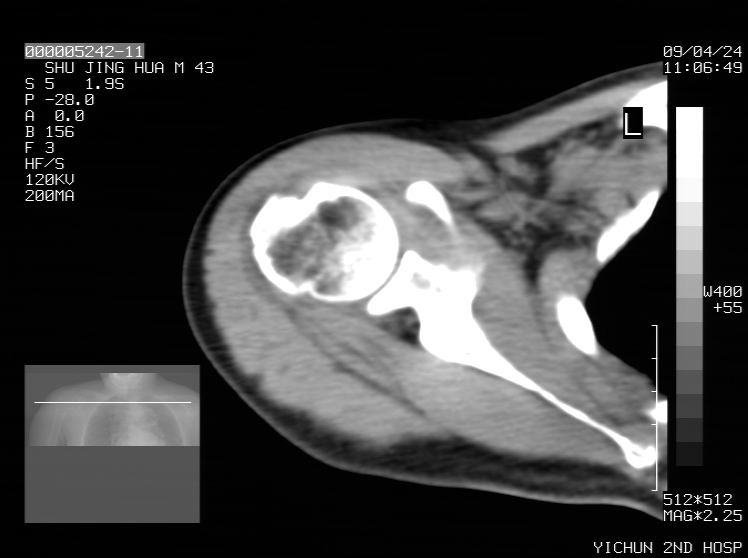

标题: CT19569:请会诊,女50岁,右肩疼痛数月 [打印本页]

标题: CT19569:请会诊,女50岁,右肩疼痛数月

考虑骨化纤维瘤

多考虑骨化性纤维瘤 。

多考虑骨化性纤维瘤

钙化性肌腱炎

是指钙盐沉积在变性肌腱中的一种无菌性炎症,常见于肩关节的肩袖肌腱,引起肩部疼痛和活动受限。分为急性和慢性两种类型,急性型有肩关节突然出现急性疼痛的发作史,夜间可痛醒。